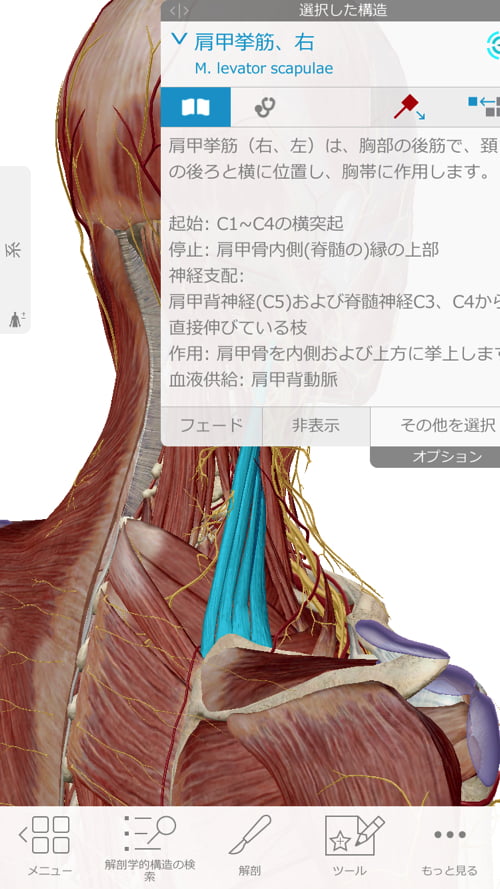

そして今回は首も凝っていて肩甲骨を引っ張ってしまっていたので調整

脇の周りの筋肉も硬直していて腕が上がらない、回せない

動かすと痛い症状を作っていました。

それらの筋肉や腱をすべて緩めて正しい位置に戻したら